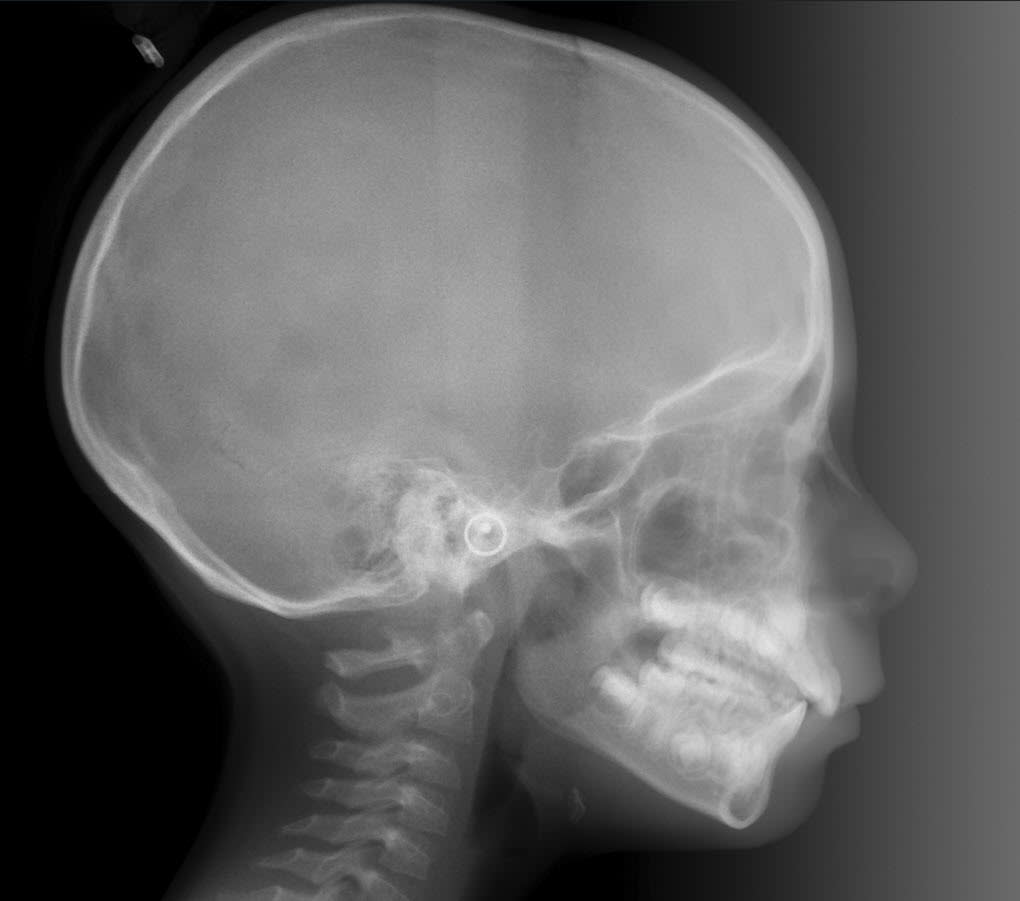

Voici les clichés radios demandés. Cette jeune fille a 7 ans.

Qu'est-ce que tu proposes ?